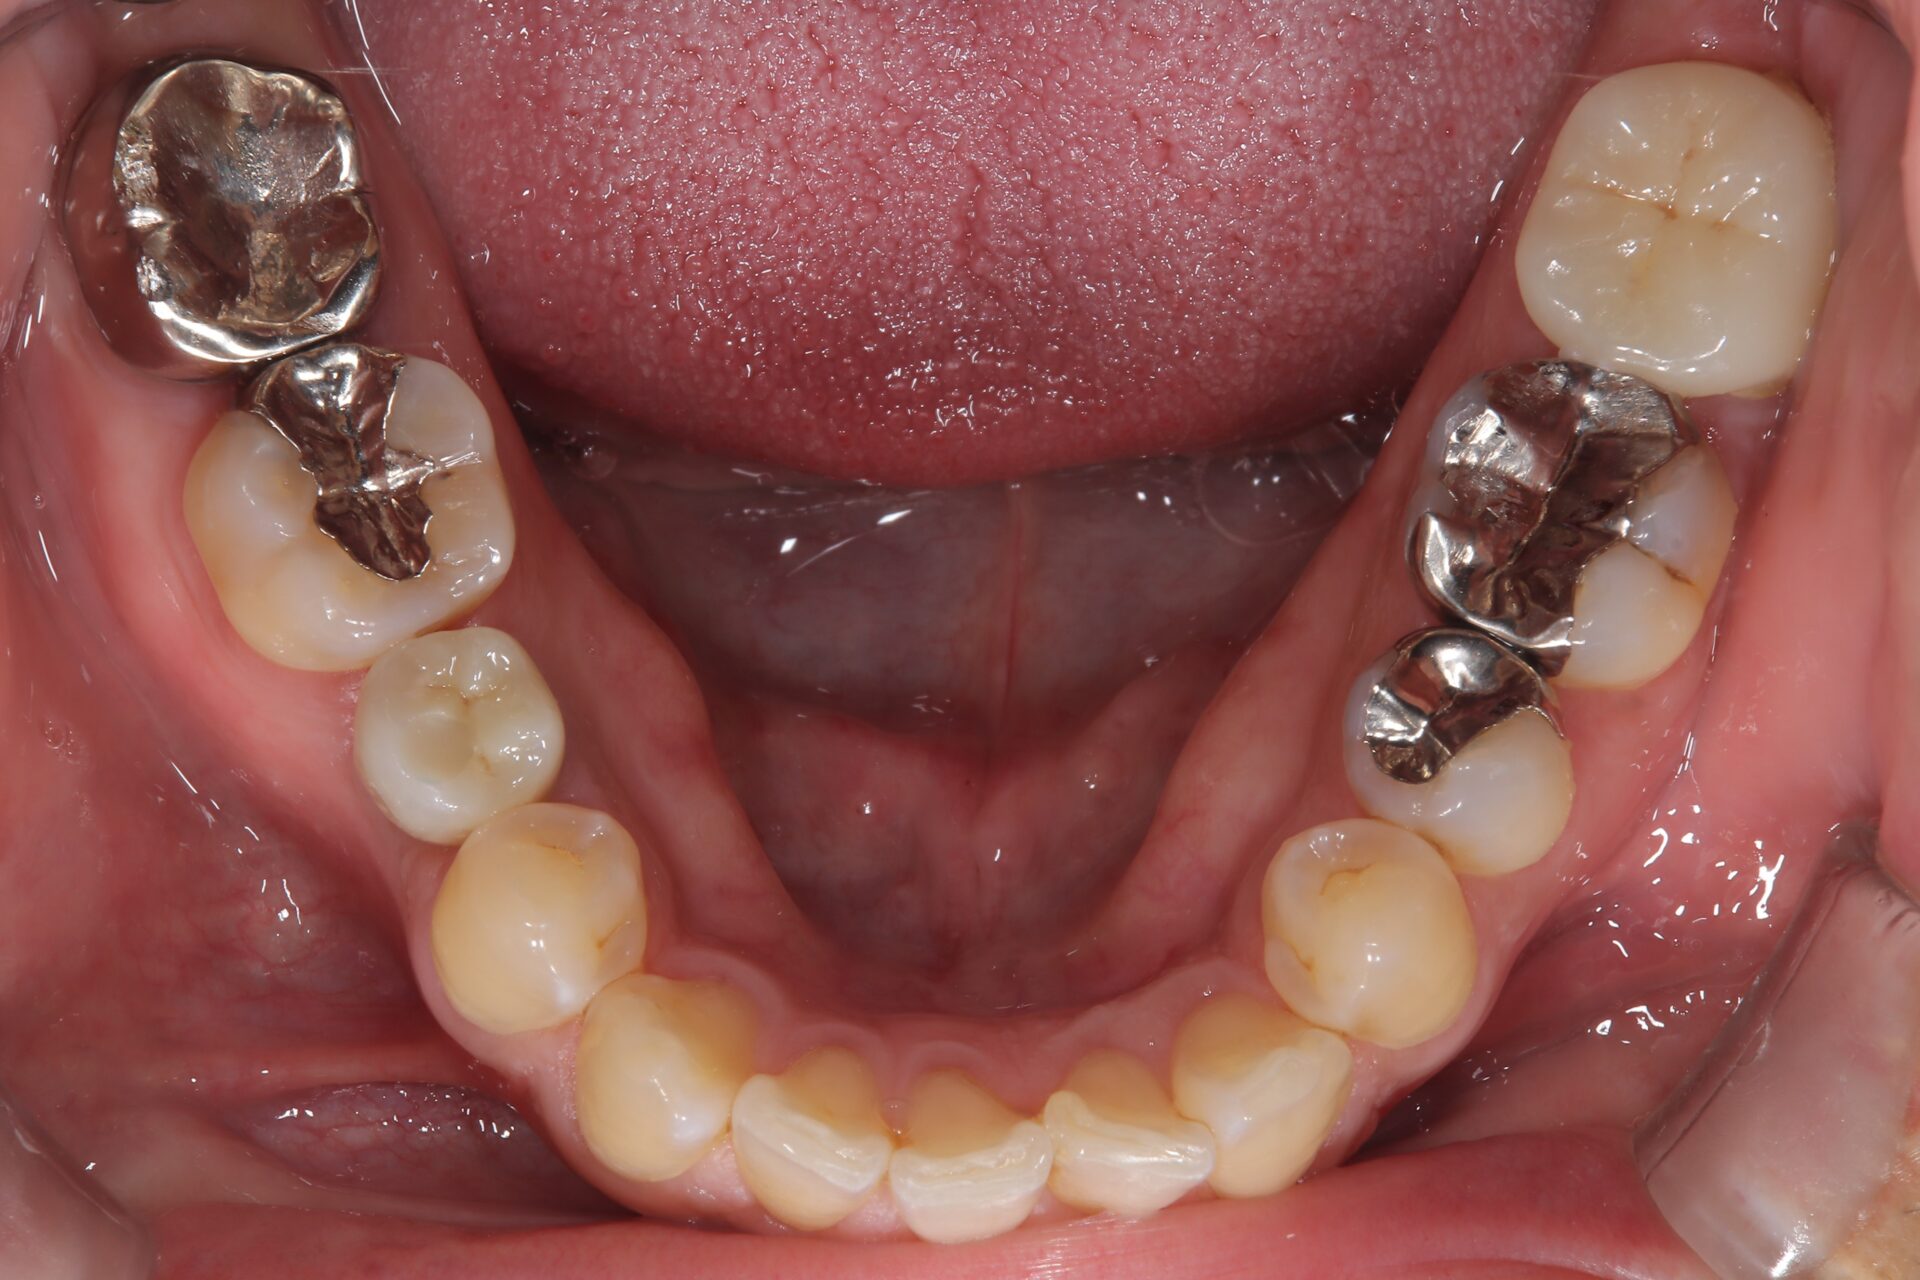

画像

R2.7

治療部位 左下6,7

費用 約700000円

治療期間 約6ヶ月

痛み、腫れを感じておりレントゲンを撮影、歯が破折している可能性がありました。

被せ物を外しヒビが確認されなければ根管治療で歯を残せる可能性があること、

ヒビがあった場合は抜歯になってしまうと説明しました。

このケースは残せる状態ではなく抜歯という選択になりましたが、できるだけ患者様のご希望に寄り添い、

治療計画をご提案できるよう最善を尽くしております。